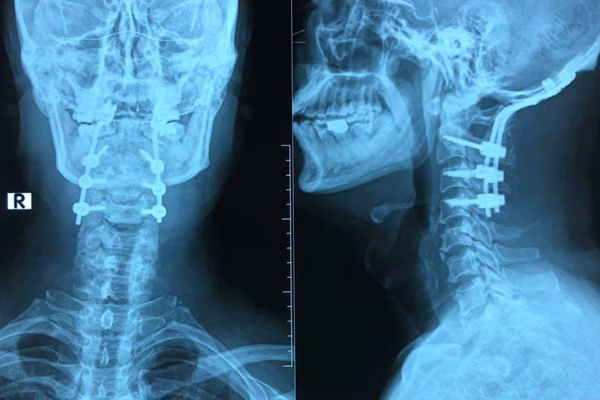

Cột sống cổ bệnh nhân được nẹp vít sau tai nạn hy hữu

Tại đây, bệnh nhân được thăm khám lâm sàng, chụp cắt lớp vi tính cột sống cổ, xác định gãy phức tạp đốt sống C1, cần được phẫu thuật cố định, làm vững cột sống.

BS Trần Quang Dũng, Khoa Ngoại thần kinh cho biết, bệnh nhân được phẫu thuật cố định chẩm - cổ. Cột sống cổ C2, C3, C4 được cố định bằng vít qua cuống cùng với vít xương chẩm, ghép xương phía sau.

Đây là kỹ thuật bắt vít có tác dụng cố định vững chắc nhất về lực. Tuy nhiên kỹ thuật này ít được thực hiện trong chuyên ngành phẫu thuật thần kinh - cột sống do tính chất phức tạp.